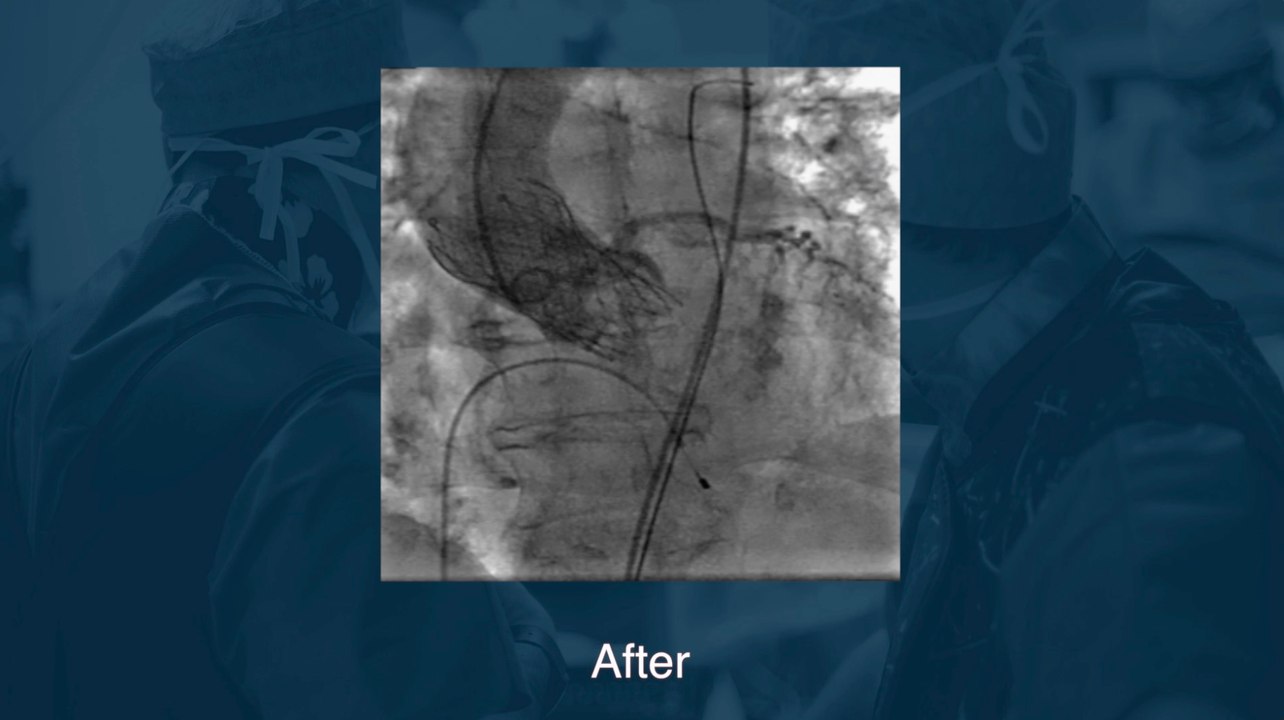

Live Case #3 : Angioplastie coronaire complexe

Journée CARDIOLIVE - Dr Durand & Dr Cador